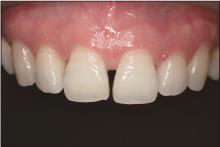

图 1

术前微笑及口内像A:微笑像;B:右侧位咬合像;C:正面咬合像;D:左侧位咬合像;E:上牙弓咬合面像;F:下牙弓咬合面像。"

图 10

术前术后的微笑像A:术前;B:术后1周;C:术后1年。"